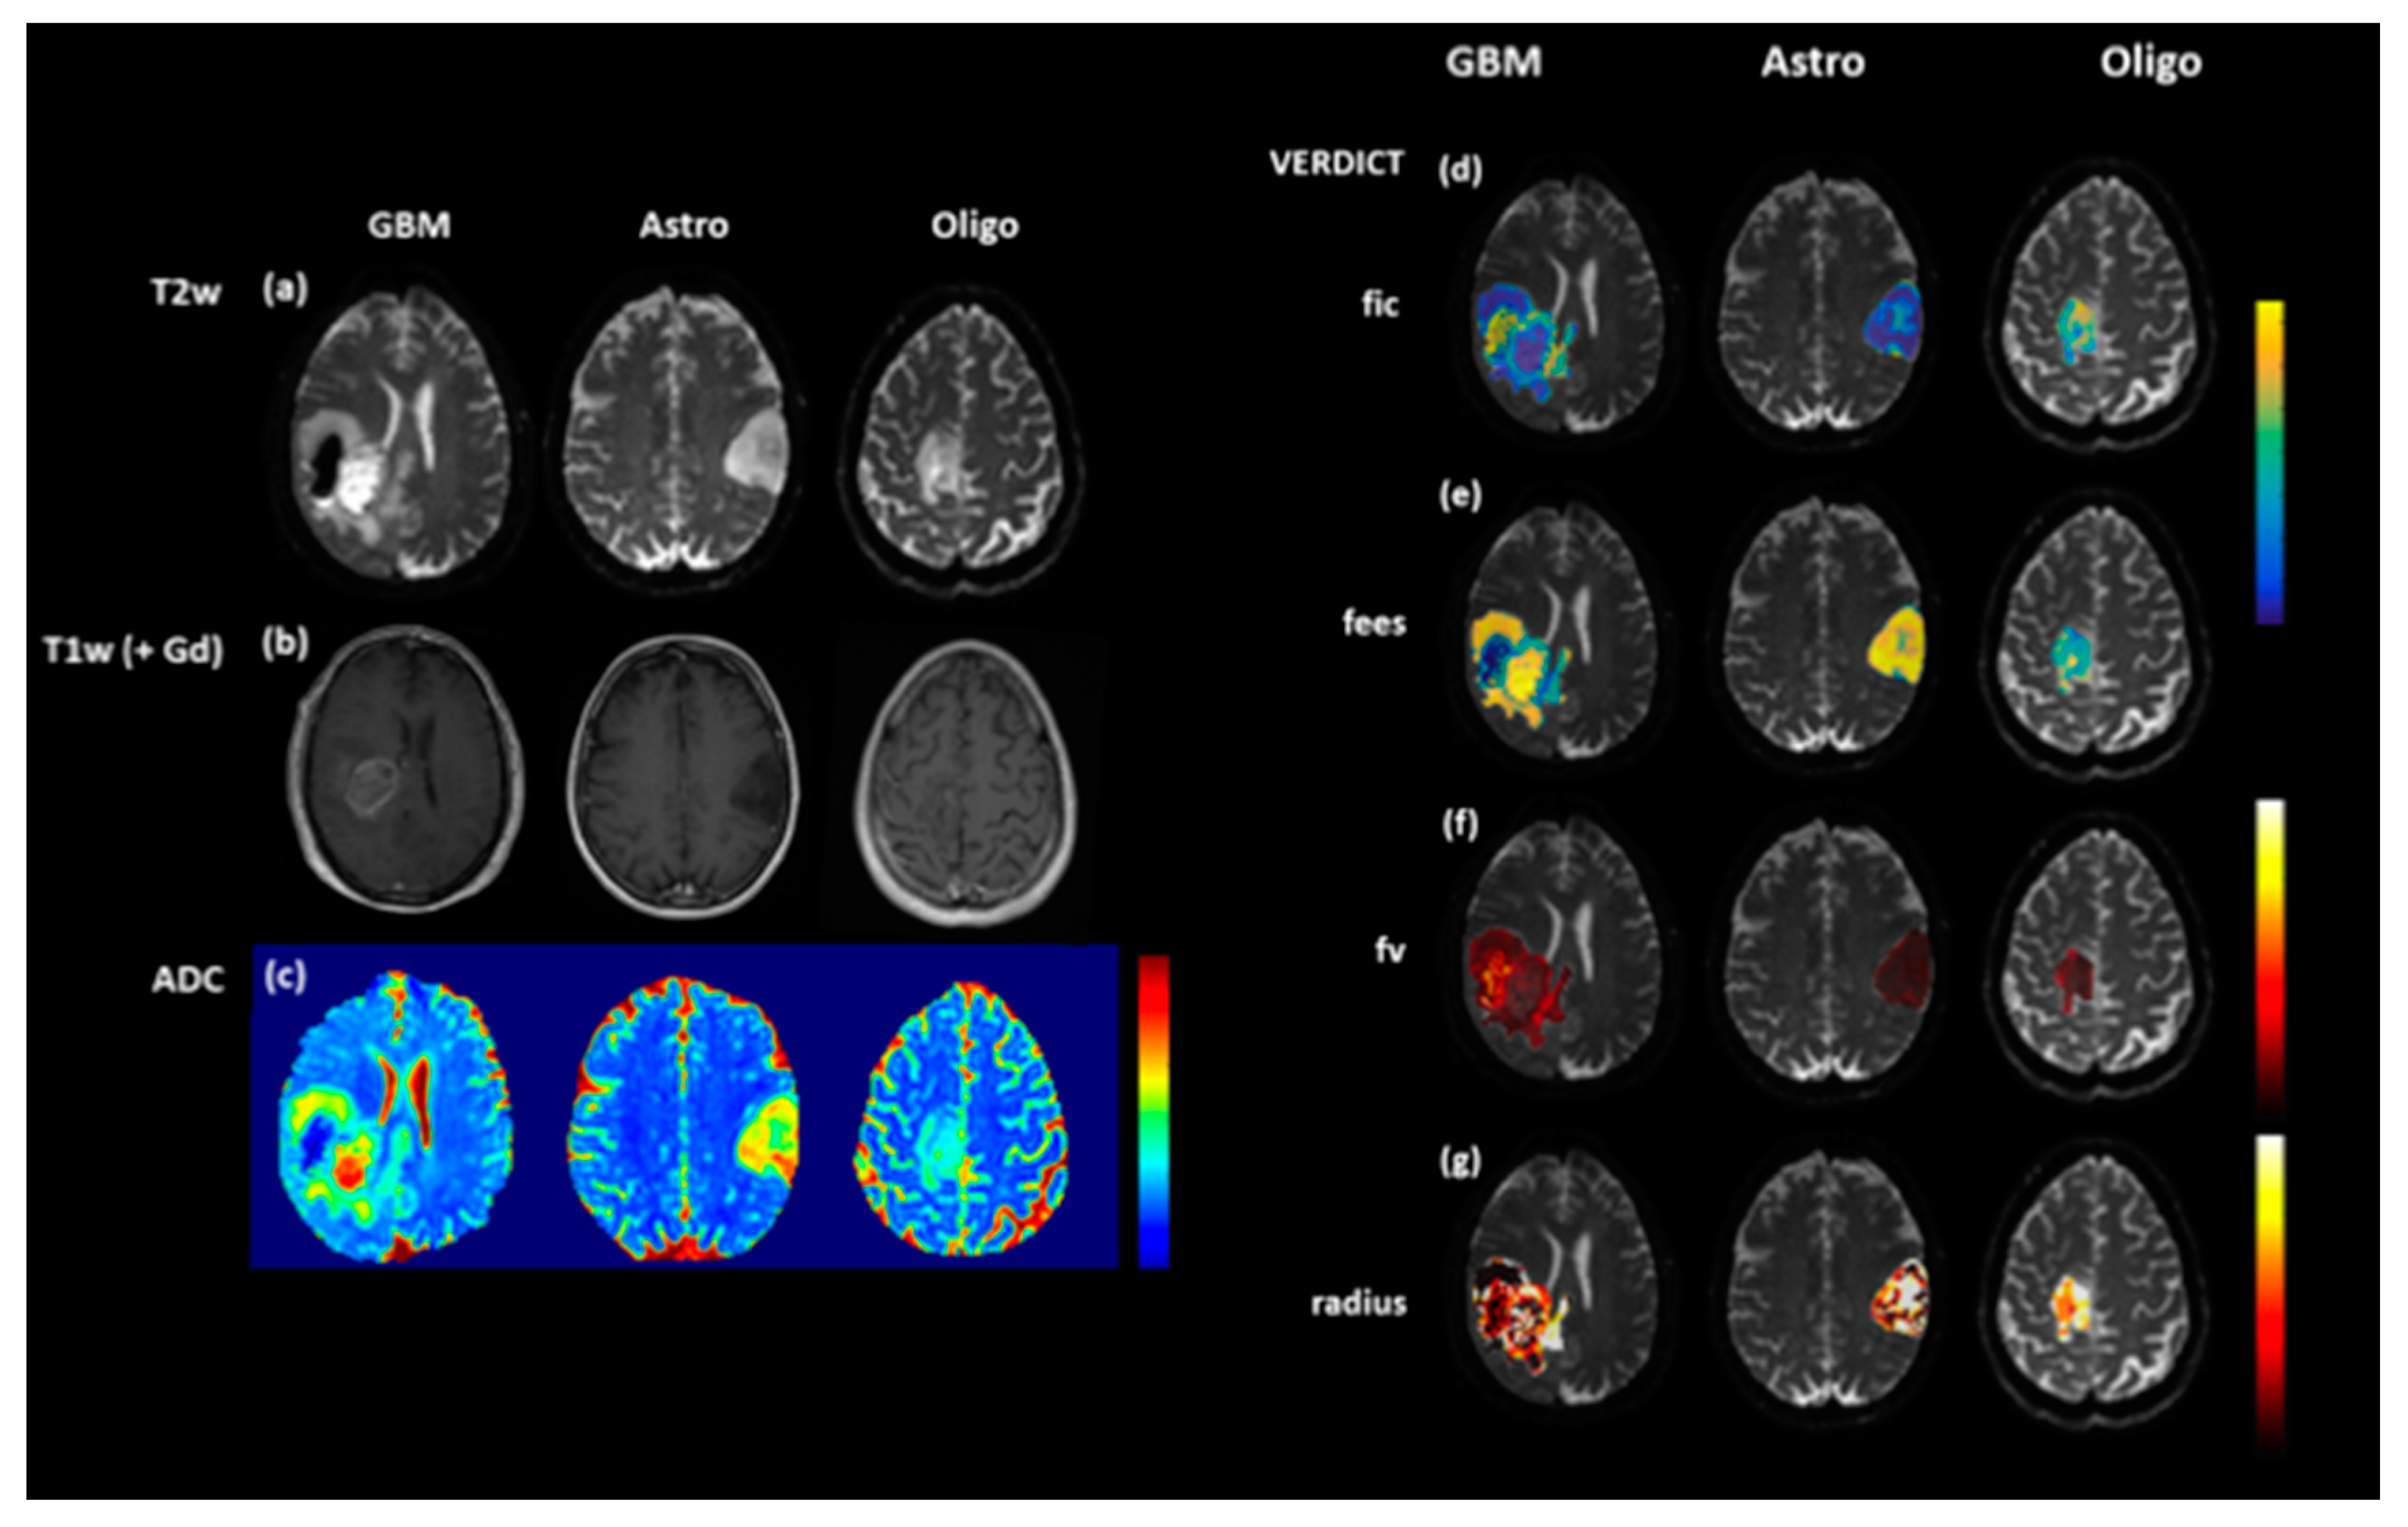

One caveat to the application of DWI for identifying non-enhancing tumour is that lower ADC values do not always correlate with increasing tumour infiltration. Low and persistent diffusion restriction can be associated with non-viable tissue necrosis. In adults, these lesions tend to be periventricular, slowly change over several months and are thought to be a type of treatment toxicity, associated with better outcomes. Novel diffusion modelling techniques such as Vascular, Extracellular, and Restricted Diffusion for Cytometry in Tumours (VERDICT) have been developed at our institution that aim to identify diffusion parameters that more accurately reflect tumour microstructure [53] and will be applied to paediatric brain tumours (Figure 2).

Figure 2.

T2-weighted (T2W (a), T1-weighted (T1W) post contrast (b) and ADC maps (c) in a range of brain tumours: glioblastoma multiforme (GBM), diffuse astrocytoma (Astro) and oligodendroglioma (Oligo). Although the ADC map for the oligodendroglioma (c) is relatively uniform, the Vascular, Extracellular, and Restricted Diffusion for Cytometry in Tumours (VERDICT) parameter map fic (intracellular fraction) (d) demonstrates increased signal at the anterior margin, thought to be a marker of increased cell density. The other VERDICT parameter maps (e) fees (extracellular, extravascular fraction), (f), fv (vascular fraction) and (g) radius (cell radius) also demonstrate tumour heterogeneity which could potentially be used to guide biopsy.